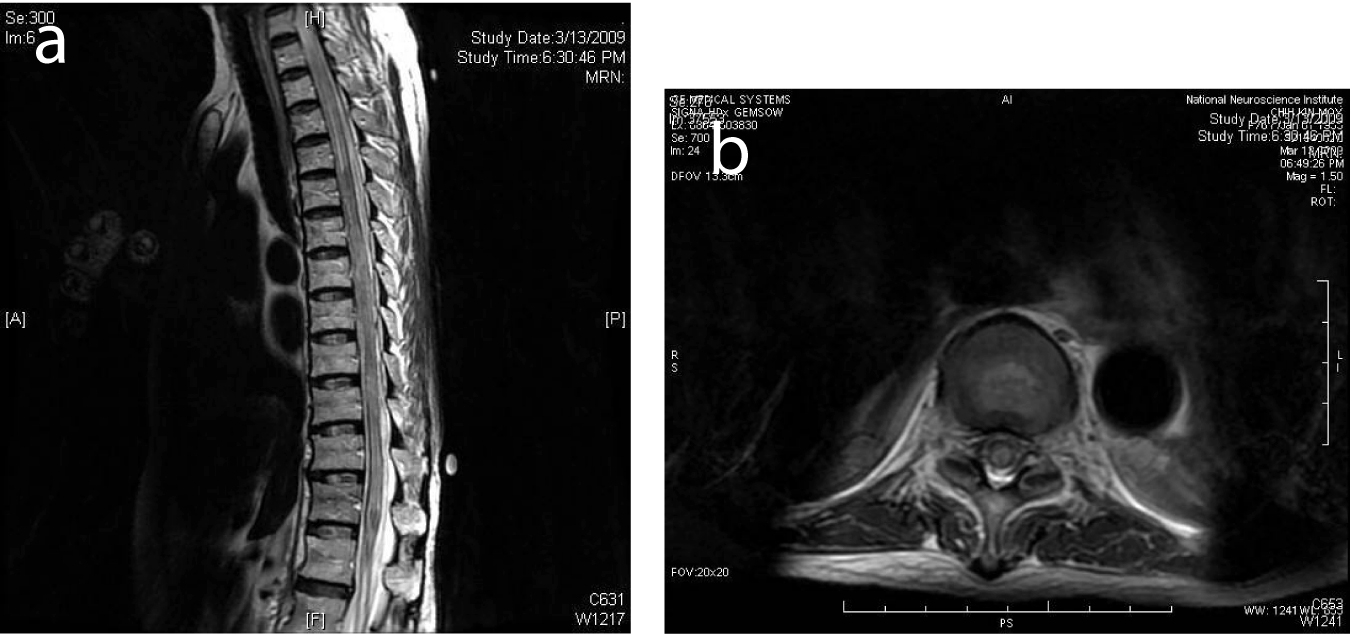

Brain Tumour In Pregnancy - Bahrain Medical Bulletin

Symptoms of brain tumor in pregnancy might be due to increased intracranial pressure, which include nausea, vomiting, headaches, seizures, visual disturbances or blindness due to ... Read Here